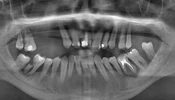

Diş Ağrısı

Diş Çürükleri

Diş Eksikliği

Diş ve Diş eti hastalıkları

Periimplantitis

Peri-İmplant Mukozitis

Çene Kistleri

Implant tedavisi